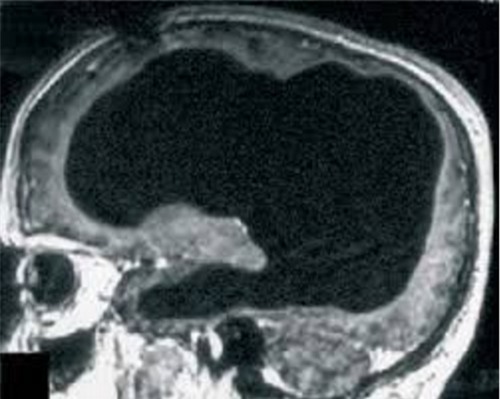

Sau khi tiến hành chụp X-quang não, các bác sĩ đã vô cùng kinh ngạc khi thấy phần lớn não bộ của người đàn ông này đã dần dần bị phá hủy trong suốt 30 năm qua bởi sự tích tụ của các chất lỏng trong não, tình trạng này được gọi là não úng thủy.

Được biết, từ khi còn là một đứa trẻ, ông đã được chẩn đoán về hiện tượng này và cũng đã điều trị bằng phương pháp đặt stent, nhưng đến khi 14 tuổi thì ông đã tháo stent ra và từ đó phần lớn não bộ của ông bị xói mòn.

Mặc dù mô não chỉ còn lại một khoảng nhỏ, tinh thần và mọi hoạt động của người đàn ông này không bị ảnh hưởng. Chỉ số IQ của ông chỉ dừng ở con số 75 điểm, nhưng ông vẫn rất minh mẫn và luôn hoàn thành tốt công việc công chức của mình. Hiện tại ông đã kết hôn và có hai con, sức khỏe của ông tương đối khỏe mạnh.